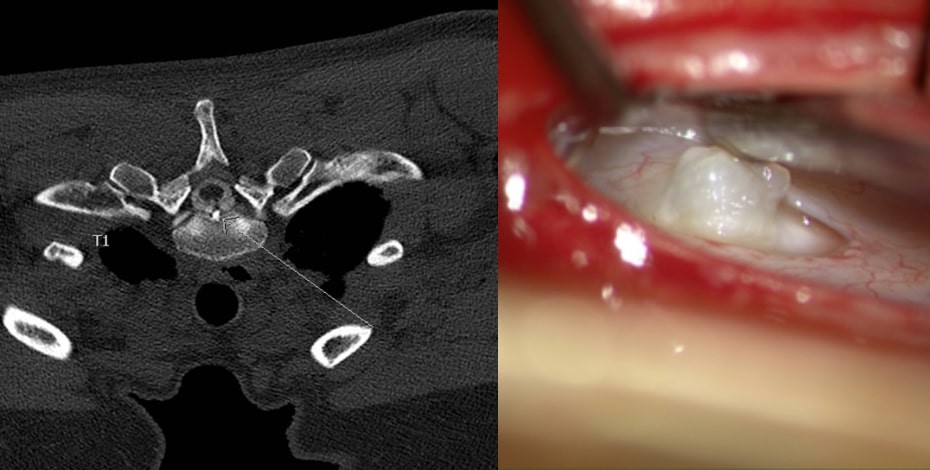

MRI and intraoperative image of the same patient showing a large bone spur and the defect where it perforated the dura. Images courtesy of Dr Scott Davies